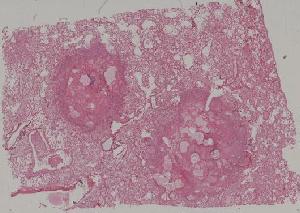

低倍视野

76. Acute pyelonephritis

77. Chronic pyelonephritis

41. Opportunistic infection in the lung

71. Acute transplant rejection of kidney

72. Lupus nephritis